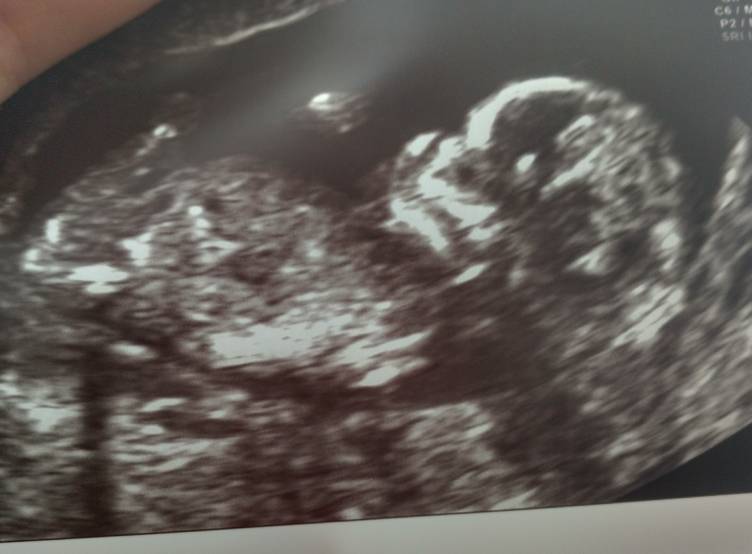

♥♥♥♥♥♥♥♥♥♥♥♥♥Moja kolejna miłość [emoji3531]

To takie niesamowite, a jednak każdej z nas w jakiś sposób odebrane. Dobrze, że możemy walczyć o swój indywidualny cud na tym świecie. Zobacz załącznik 975774